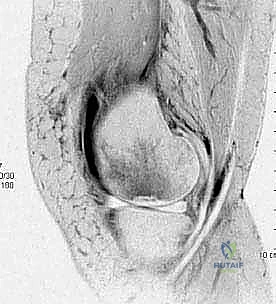

3. التصوير بالرنين المغناطيسي (MRI) – المعيار الذهبي

لا يمكن تقييم الغضروف المفصلي بدقة باستخدام الأشعة السينية. هنا يأتي دور الرنين المغناطيسي العالي الدقة. يُعد الرنين المغناطيسي حجر الزاوية في خطة الأستاذ الدكتور محمد هطيف التشخيصية، حيث يسمح بـ:

* تقييم حالة الغضروف المفصلي (هل هو سليم، متورم، أم ممزق؟).

* تحديد مدى ثبات القطعة العظمية (في حالات OCD). وجود سائل بين القطعة والسرير العظمي في صور T2 يشير إلى عدم الاستقرار.

* اكتشاف الوذمة العظمية (Bone Marrow Edema) التي تميز حالات SONK و AVN في مراحلها المبكرة قبل ظهورها في الأشعة السينية.

* تحديد حجم وعمق الآفة بدقة مليمترية للتخطيط الجراحي.